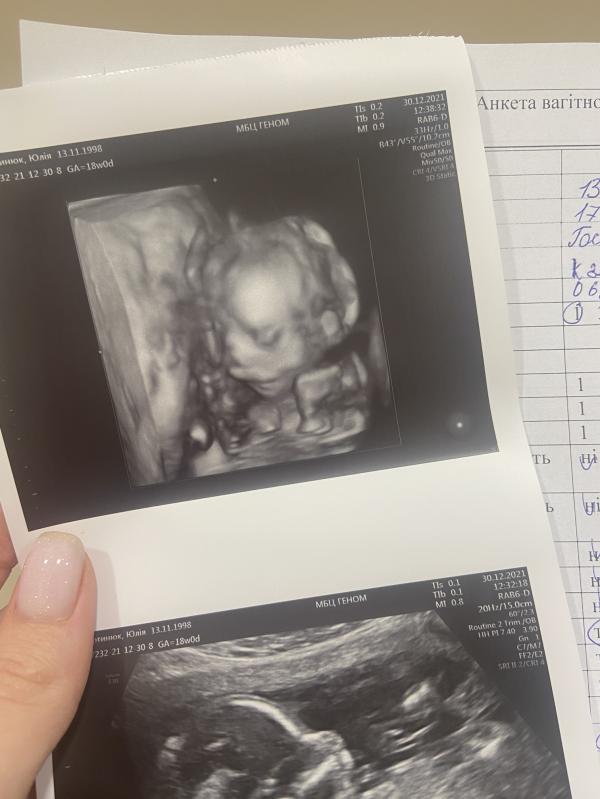

30.12.2021

Наш 2 скринінг ❤️ все в нормі, робили комбінований в Геномі, чекаю ще результати по крові

Бейбік важить 230 г🥺 такий харошенький❤️Конверт вже в нас, будемо лопати гендер шар в новорічну ніч, це буде найкращим подарунком для нас🙏🏻